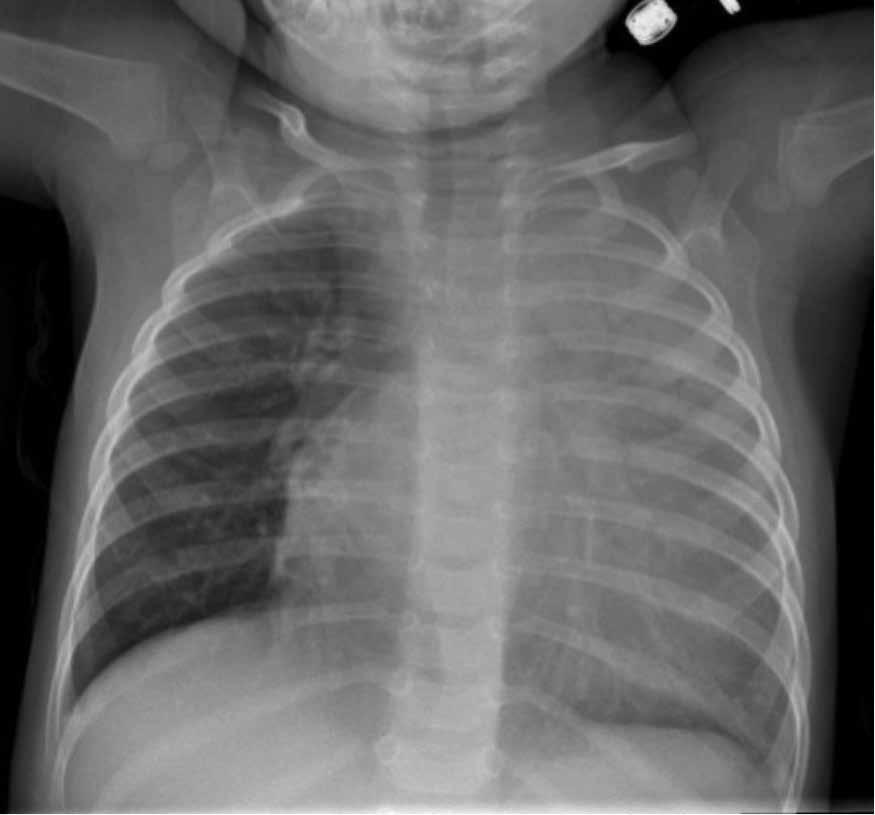

What’s the diagnosis?

An 11-month-old male infant was admitted to the PICU with a history of recurrent respiratory infections, including pneumonia and otitis media. The patient had been experiencing these infections since the age of 6 months, despite appropriate antibiotic therapy. Additionally, he exhibited poor weight gain and failure to thrive.

Upon examination, the patient appeared pale and had mild retractions, with diffuse wheezing, and crackles and diminished breath sounds on the left. Chest X-ray revealed opacification of the left lung and cardiac enlargement. CT of the chest revealed left upper lobe consolidation as well globular enlargement of the left ventricle with marked outpouching of the left ventricular apex with associated myocardial thinning.

Laboratory investigations revealed low serum immunoglobulin levels, including markedly reduced levels of IgG, IgA and IgM. Flow cytometry analysis of peripheral blood revealed the absence of mature B cells.

What’s your diagnosis?

A. X-linked (Bruton) agammaglobulinemia (XLA)

B. Common variable immunodeficiency (CVID)

C. Severe combined immunodeficiency (SCID)

D. Chronic granulomatous disease (CGD)

Have you figured out the diagnosis?

See Page 23 for the answer.

Answer: A) X-linked (Bruton) agammaglobulinemia

Given the incidental finding of the ventricular aneurysm, further investigations were initiated. Based on the clinical presentation, cardiac findings and laboratory results, a provisional diagnosis of Bruton agammaglobulinemia was suspected. Confirmation of the diagnosis was made through genetic testing, which identified a pathogenic mutation in the BTK gene.

CVID is another immunodeficiency disorder characterized by impaired antibody production. It may also present with recurrent respiratory infections, but typically manifests in older patients. Additionally, B cell numbers are usually normal or slightly reduced.

SCID is characterized by profound deficiency in both T and B lymphocytes in addition to low immunoglobulin levels. Diagnosis is facilitated by abnormal TREC numbers on neonatal screening.

CGD may present similarly to Bruton agammaglobulinemia with respiratory tract infections, but the defect is with phagocytic cells (particularly neutrophils) rather than B cells. Plus, patients may have additional clinical manifestations such as granuloma formation and abscesses.